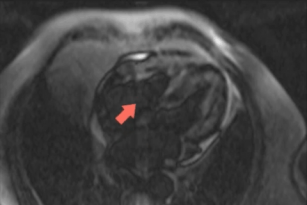

Diagnosing myocarditis with the help of CMR 26th Sep 2017 - Andrew R. Houghton, MD Learn how cardiac MRI can help you make a diagnosis of myocarditis. Taken from our CME accredited CMR Essentials ...